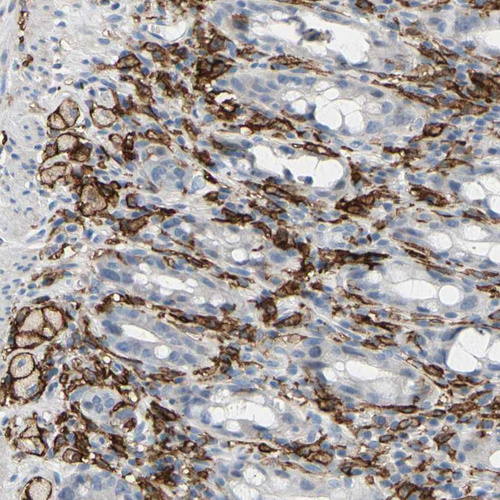

Immunohistochemical staining of human lung shows strong cytoplasmic/membranous positivity in macrophages.